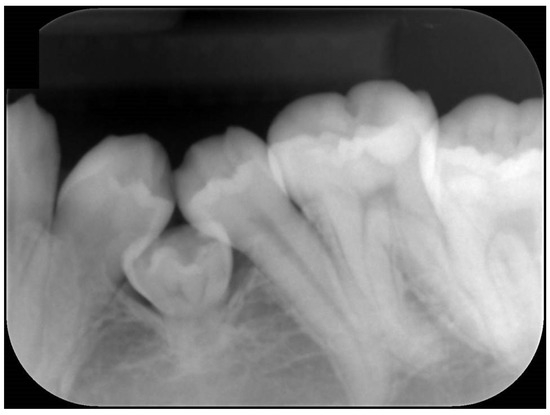

The treatment was carried out under general anesthesia with the aim of improving his oral hygiene. Initial observation of his oral condition was carefully completed. Dental X-ray and intraoral images during the administration of analgesic were obtained before starting the surgery (Figure 2 and Figure 3). A local anesthetic, proparacaine hydrochloride/felypressin (Citanest-Octapressin Cartridge for Dental use®), was injected into the affected area. An incision was made around the area along the cervical region and the oral mucosa was removed, which revealed the concealed tooth. It was observed from the left buccal side, but it was considered to be partially ankylosed. Then, a part of the target tooth was histopathologically examined to determine if there was any sign of ankylosis around it. Eventually, the tooth was divided into parts for smooth extraction, and the incision was closed using absorbable sutures (Figure 4).

Figure 3. Intraoral images obtained under general anesthesia. These revealed two missing congenital lateral mandibular incisors.